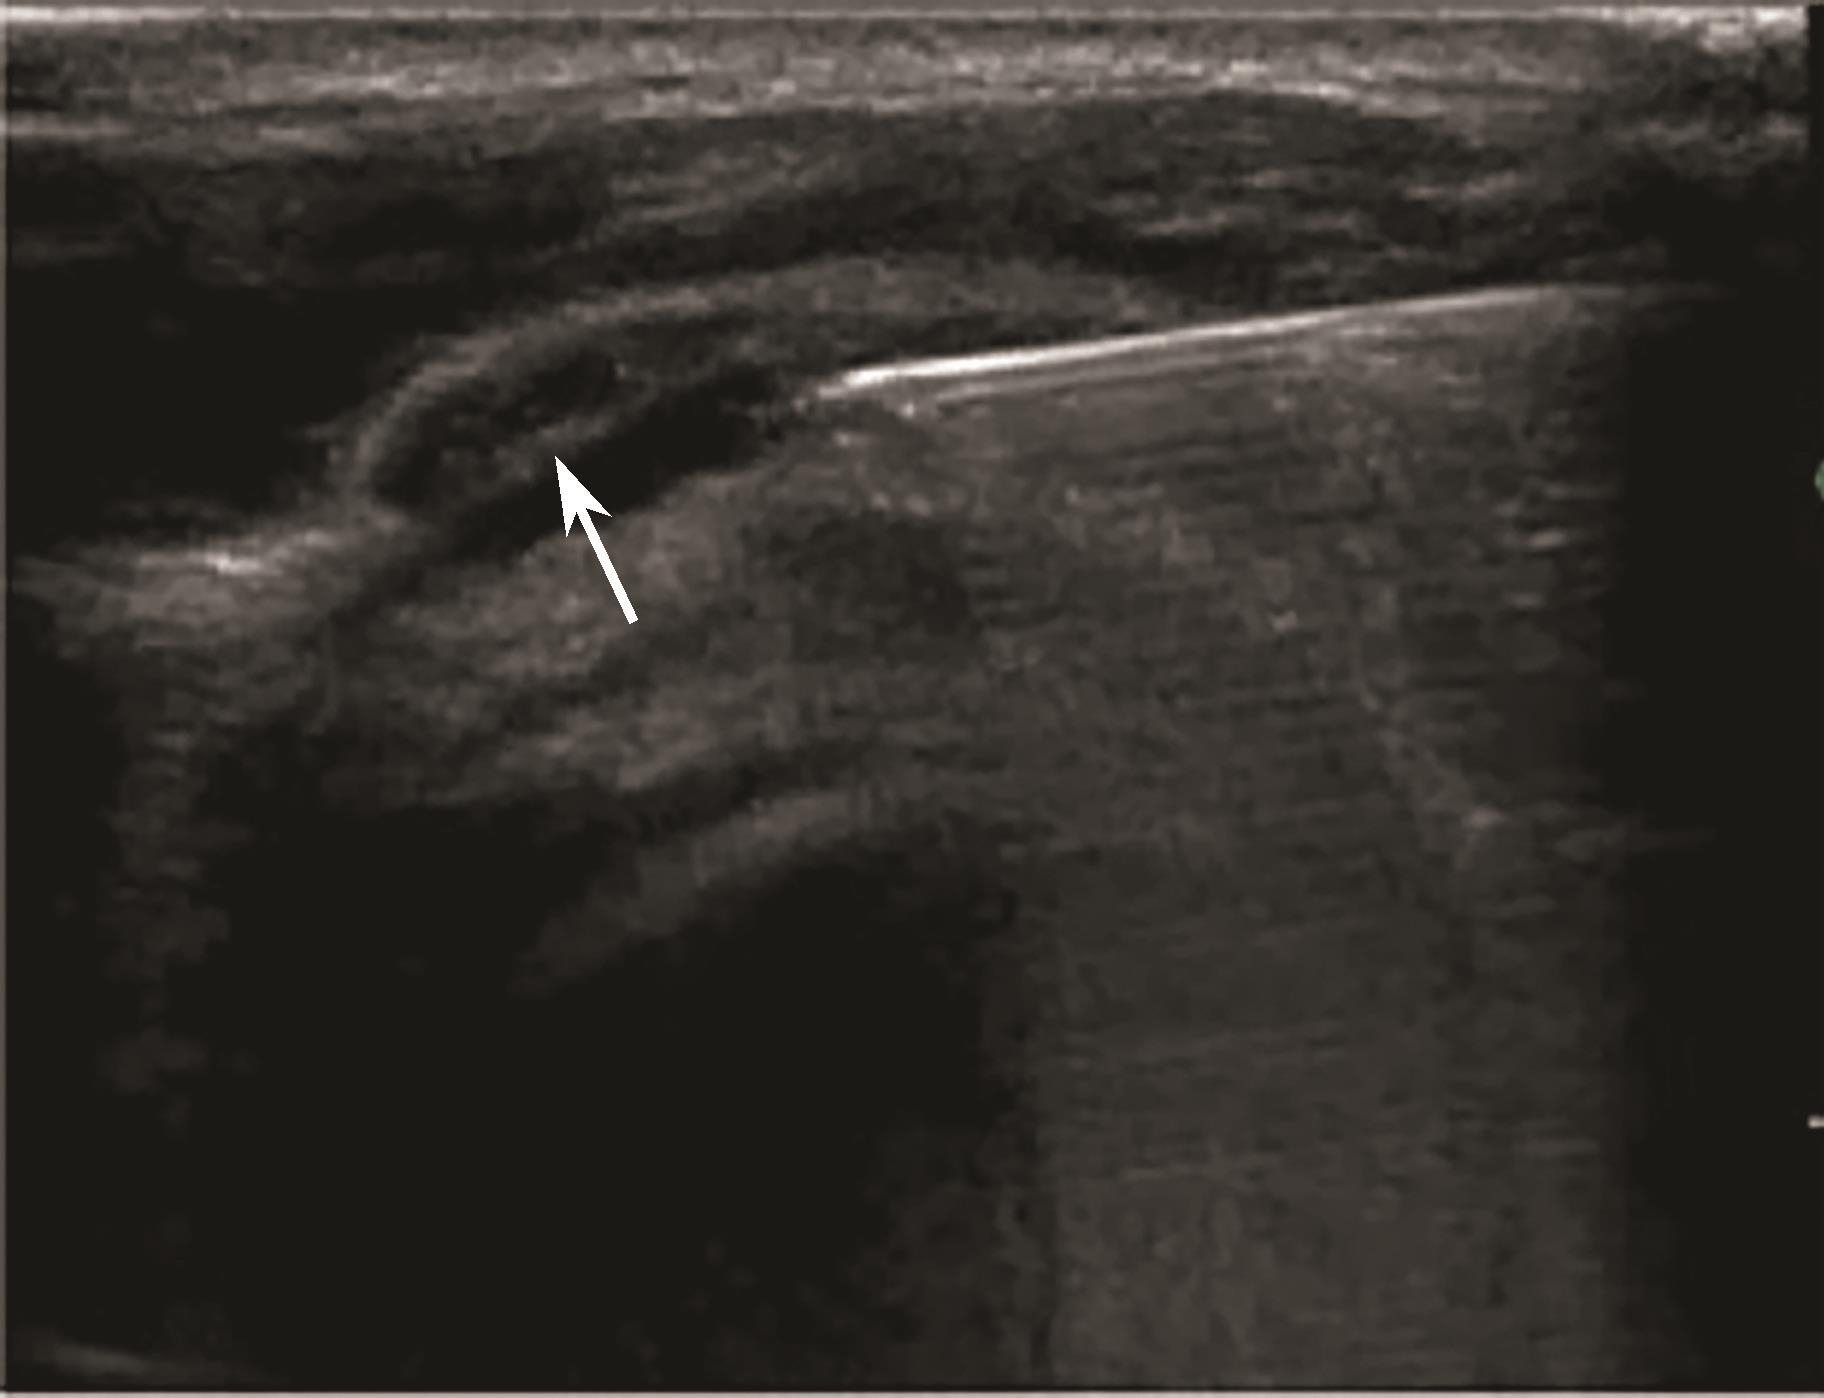

2.当针尖进入滑囊后(图2-1-5),可推注少量药物,若推注顺利可观察到滑囊扩张及药物的弥散(图2-1-6),同时也表明针尖准确位于滑囊内,可继续推注混合药物3~5ml。若推注受阻,原因有可能是针尖在滑囊组织内,需重新调整针尖,也可能是滑囊内粘连明显所致,可加大力度,利用液体推注的压力松解粘连,松解后可见粘连带呈线状稍强回声(图2-1-7),也可在粘连远端重新选择部位注入药物,这类患者可能需要多次治疗才能达到较好的疗效。

▲ 图2-1-5 超声引导下肩峰下-三角肌下滑囊穿刺治疗超声图

箭头:显示穿刺针尖进入滑囊;星号:冈上肌腱;H:肱骨头